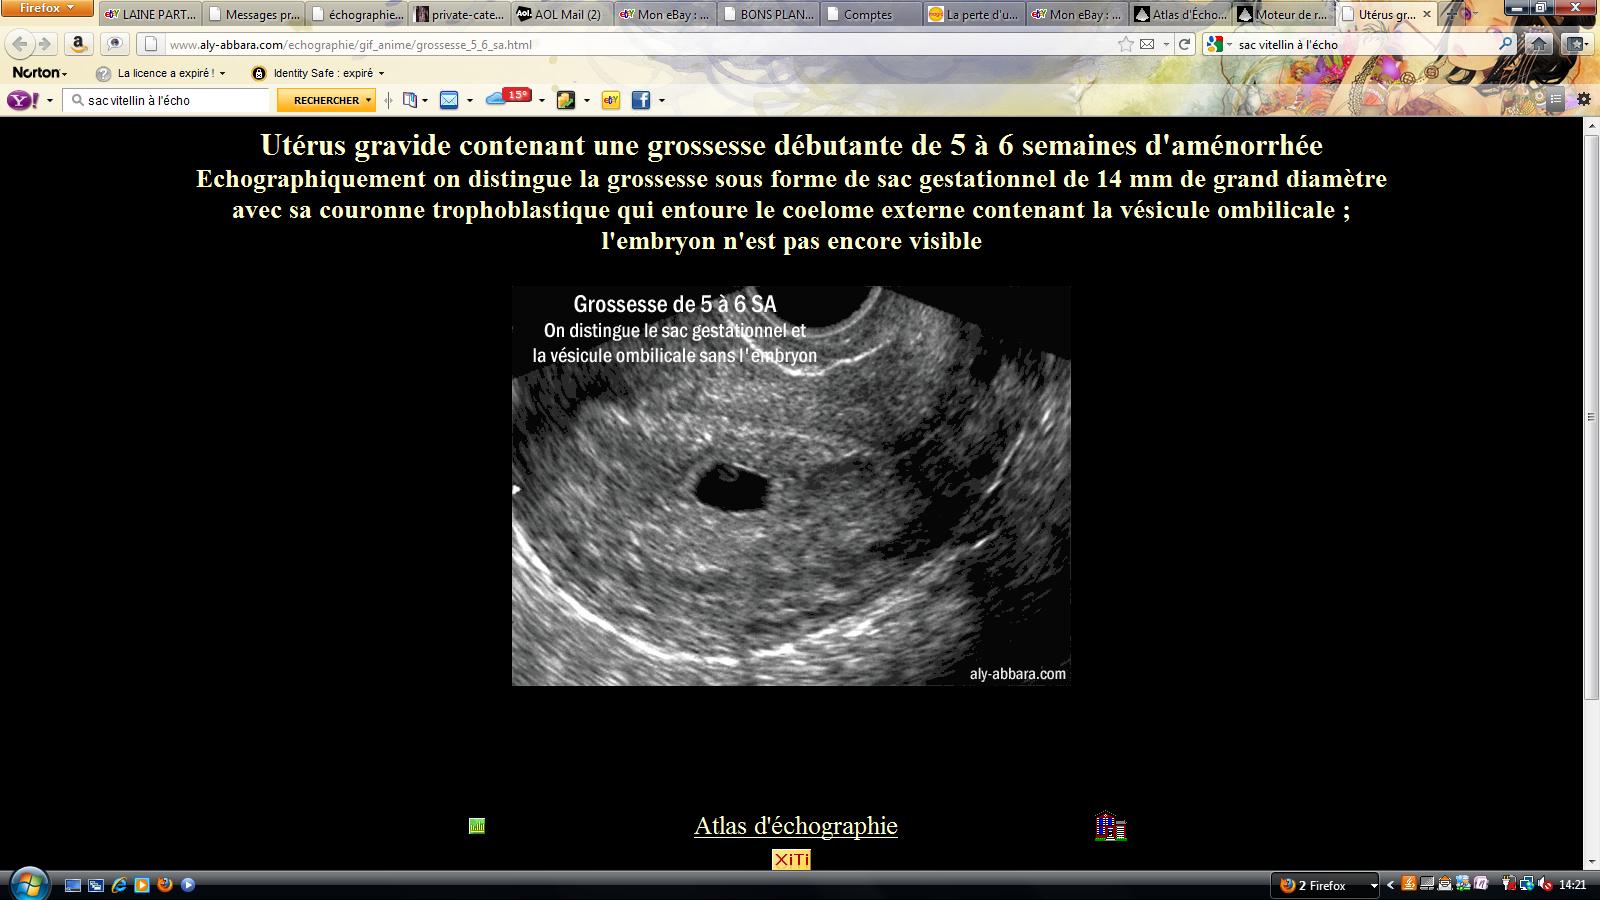

Trois échographies de dépistage sont recommandées aux femmes enceintes à chaque trimestre de la grossesse. Dans le cas d’une grossesse intra utérine d’évolution incertaine (sac gestationnel intra-utérin < 25 mm) sans vésicule vitelline visible, l’absence d’apparition d’un embryon avec une activité cardiaque à l’échographie endovaginale dans un délai d’au moins 14 jours permet d’affirmer que la grossesse est arrêtée (Grade C). Il mesure alors 2 à 3 mm.L'utilisation de la voie endovaginale est souvent nécessaire pour le voir.

Pour les oeufs clairs (grossesse non évolutive) l'expulsion se fait généralement naturellement (règles presques normales), on controle parfois par une échographie que l'utérus est bien vide et si ce n'est pas le cas on peut procéder à un curetage. La gynéco confirme mes doutes, elle me dit que l’embryon a 1 mois de retard par rapport au terme calculé depuis mes dernières règles. Mon sac gestationnel est 14 mm et l'embryon serait de 2 mm.